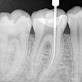

• Root Canal Treatment: If you have a tooth infection due to decay or injury, a root canal may be necessary.